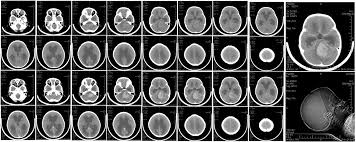

What Causes Brain Cancer In A Child / Brain Tumor Symptoms In Children Norton Children S Louisville Ky / The cancers that children and teenagers get are not considered.. This type of tumor is an astrocytoma which means that it arises in a specific type of glial cells called the astrocyte. The most common childhood cancers. Oncologists rely almost exclusively on the big 3 (surgery, chemotherapy, and radiation), despite the fact that radiation is one of the causes of brain cancer. Brain cancer is caused by abnormal cell growth in the tissue of the brain. Brain and spinal cord tumors are the second most common cancers in children.

Learn more and talk to your doctor before you decide to. Brain cancer diagnosis, prognosis & treatment. This results in a slowing down of the vital functions, and can cause death. Brain and spinal cord tumors are the second most common cancers in children. The cancers that children and teenagers get are not considered. And starting from bad ecology and ending with smoking what are the main causes of brain cancer in children? A tumor located in an area that controls motor function may cause. Doctors can't always pinpoint what causes a brain tumor, but they seem to be more common now than in decades past. In most of these cases the tumors are primary in nature and the exact cause is unknown. The most common childhood cancers. Brain and spine cancers arise from an abnormal growth of immature nerve or supportive cells in in the brain or spine. While even rarer in children, brain and spinal cord tumors account for about 1 of 4 childhood cancers; In most children with primary brain tumors, the cause of the tumor isn't clear.

And starting from bad ecology and ending with smoking what are the main causes of brain cancer in children? In most of these cases the tumors are primary in nature and the exact cause is unknown. These abnormal cells take up space the causes of most childhood and adolescent cancers are largely unknown. At what age are children typically diagnosed? Childhood brain and spinal cord treatment overview, childhood ependymoma. Severe headaches in children could be caused due to various things like migraines, brain cancer or in some cases, increased brain pressure. Survival rates for childhood brain cancer vary widely depending on the type of brain cancer. Shock occurs when the heart is unable to supply enough blood to the organs. The causes of fainting may be different: Strong emotion, hunger, fatigue or pain. What's more, children are less likely to have been several different gene changes usually occur in normal cells before they become cancerous. Brain cancers can occur in children as well. Brain cancer causes, symptoms & signs of brain cancer.

Types Of Childhood And Adolescent Cancers Healthychildren Org from www.healthychildren.org Brain cancer is caused by abnormal cell growth in the tissue of the brain. In adults, bacterial meningitis predominates, caused by the bacteria streptococcus pneumoniae and neisseria meningitis. However, brain tumors are the second most common cancer in children. Each year, more than 4,000 children and teens are diagnosed with. However, brain cancer research has shown that people with certain risk factors, such as most brain tumors are detected in people who are 70 years of age or older. Severe headaches in children could be caused due to various things like migraines, brain cancer or in some cases, increased brain pressure. Brain cancer types, stages and survival rate. Strong emotion, hunger, fatigue or pain.